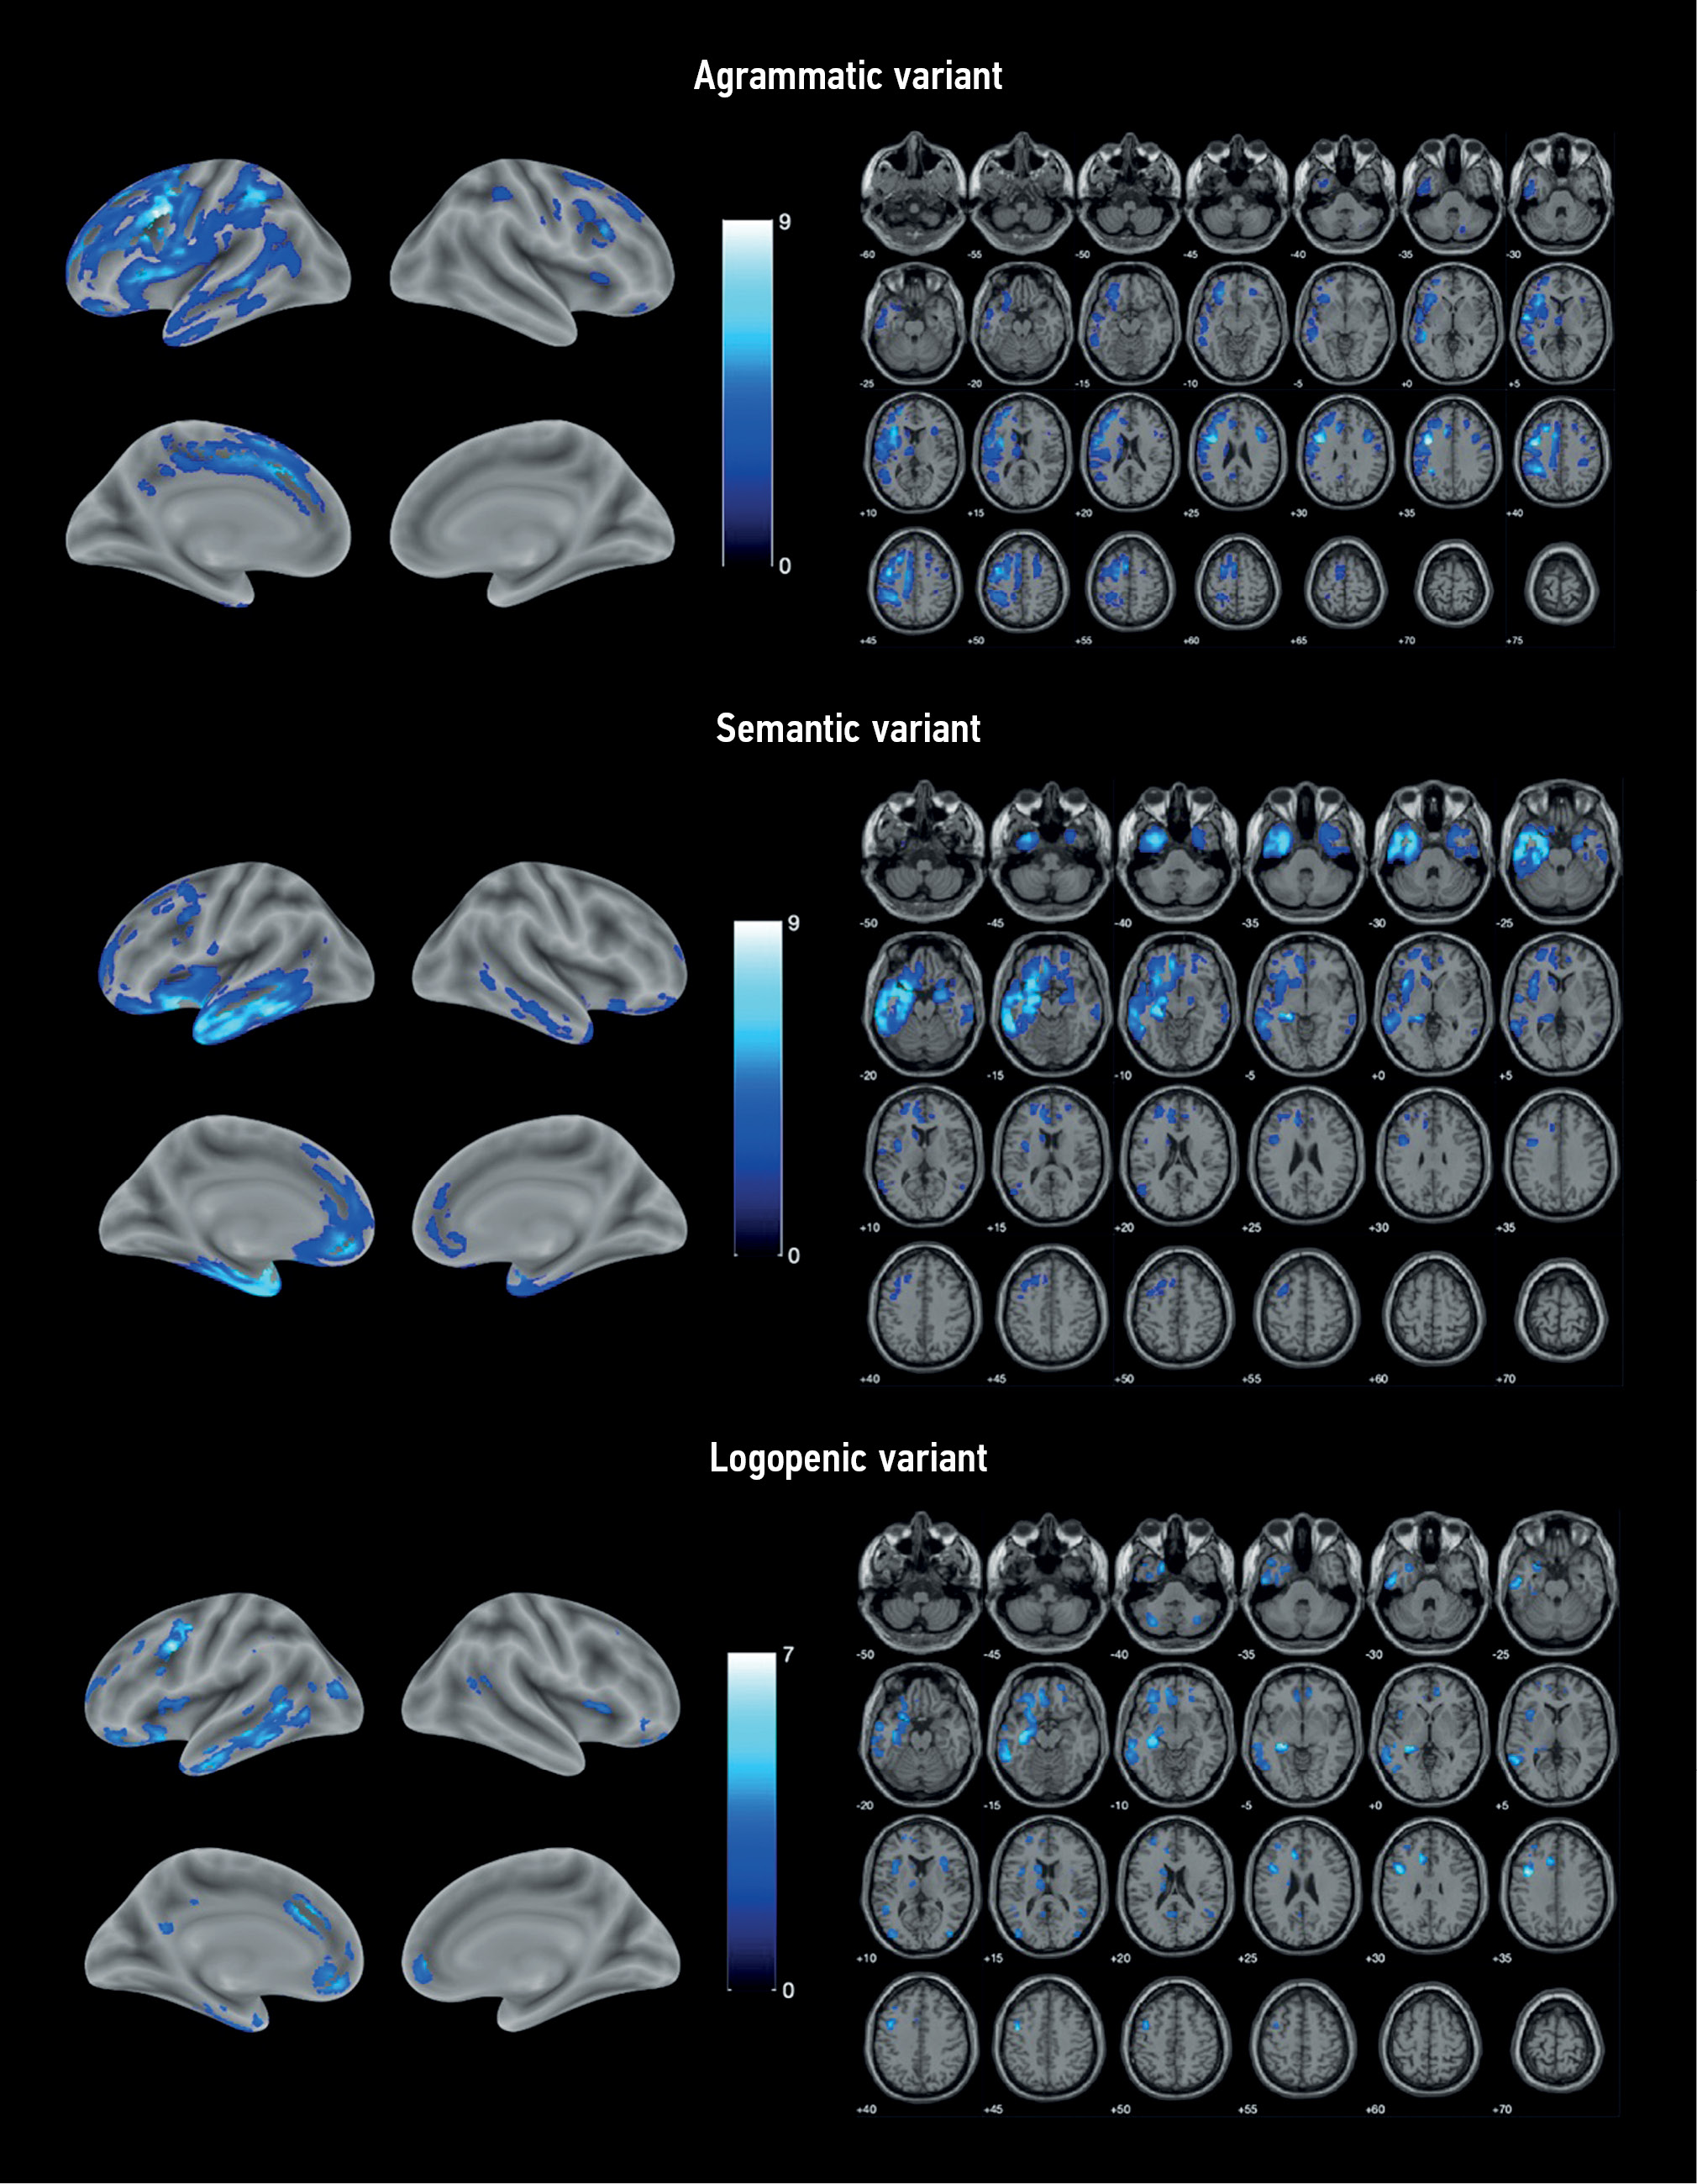

VBM identified areas of atrophy in each PPA variant compared with the control group (Fig. 1). Atrophy in all cases was asymmetric, prevailing in the left hemisphere.

Fig. 1. Localization of the areas of the loss of the gray matter volume in variants of primary progressive aphasia vs. control group. The color coding is for the T-value.

AV-PPA group: The atrophic “core” was localized in the left IFG and precentral gyrus (Table 2). Significant changes were also observed in the SMA, premotor cortex, orbitofrontal cortex (OFC), and insular cortex of both hemispheres. The temporal lobe was mainly involved in the MTG and inferior temporal gyrus (ITG), continuing into the area of the temporoparietal junction and inferior parietal lobule. In addition, atrophic involvement of subcortical structures was observed, namely, the left caudate nucleus, thalamus, putamen, and cerebellum.

SV-PPA group: Atrophy was predominantly localized in the left temporal lobe, including its pole, inferior–lateral and medial regions, and left hippocampus and insula (Table 3). Individual lesions were observed in the left frontal lobe, including the OFC, medial prefrontal cortex (mPFC), premotor cortex, precentral gyrus, and IFG. Overall, the changes were more localized than in AV-PPA and were limited to the frontal, temporal, and insular cortices, except for an atrophic lesion in the left caudate nucleus. Similar but less extensive atrophic areas were identified in the right hemisphere.

LV-PPA group: The most pronounced loss of the GM volume was also localized in the left temporal lobe but was mostly involved in the posterior parts of MTG and ITG and, to a lesser extent, the temporal pole. In addition, it continued into the parahippocampal gyrus, hippocampus, and amygdala (Table 4). Atrophy was the most pronounced in the precentral gyrus, anterior cingulate cortex, OFC, and mPFC. Apart from the frontal and temporal lobes, atrophy in this PPA variant involved the insular lobes, left parietal and occipital lobes, cerebellum, and left caudate nucleus.